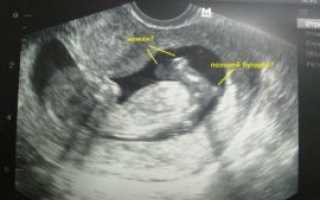

На УЗИ, которое проводят на 15-й неделе беременности будущей матери видно, как активно двигает малыш ручками, ножками. Этот срок характеризуется усиленным развитием мышечной системы.

При удачном расположении плода врач-сонолог может сказать пол ожидаемого малыша. УЗИ на 15-й неделе позволяет проследить за активностью ребенка.

На экране же малыш выглядит длиною около пальца. Если выполняют 3D УЗИ, то на экране видно недовольство крохи, которое проявляется при нажатии на живот датчиком. Ребенок может хмурить бровки, хвататься за пуповину, активнее двигаться.

На 15 неделе беременности пол будущего малыша можно определить с помощью аппарата ультразвукового исследования. Однако следует отметить, что на таком раннем сроке весьма вероятна ошибка в результатах УЗИ.

Невзирая на то, что на 15 неделе половые органы крохи уже начинают формироваться, рассмотреть их можно только на самом современном оборудовании.